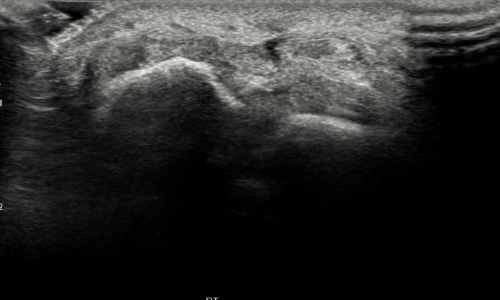

거대 세포종

힘줄 막에 생기는 종양으로 손가락에는 악성종양이 생기는 경우가 매우 드물기 때문에 보통은 양성의 종양을 말합니다. 양성의 성격을 보이지만 주변 조직을 파괴하고 높은 재발률을 나타내며 악성의 성격을 일부 보여서 반드시 치료를 해야 하는 종양입니다.

결절종 다음으로 많이 발병되는 종양으로 주로 손가락에 나타나지만 무릎이나 엉덩이(고관절)에 발병하는 경우도 있습니다.

거대세포종 초음파 영상 사진